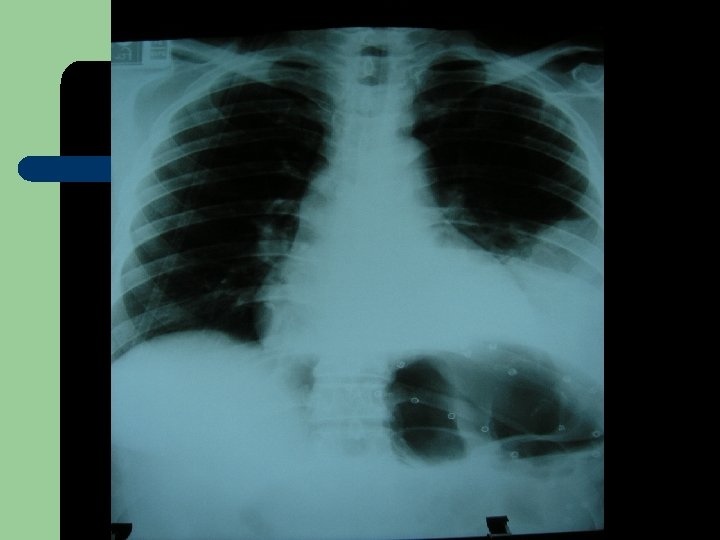

Laparoskopik Diafragma Hernisi